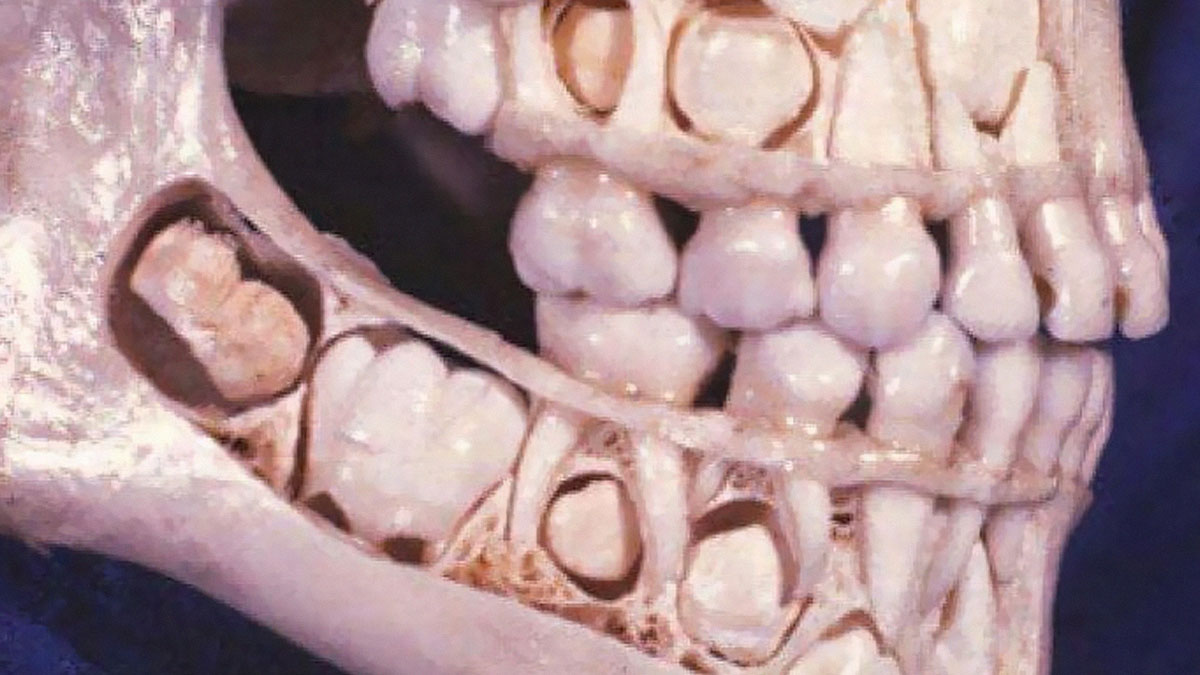

A child's skull before losing baby teeth

Mulberry molars are a dental condition usually associated with congenital syphilis, characterized by multiple rounded rudimentary enamel cusps on the permanent first molars. Mulberry molars are physically defective permanent molars. The deformity is caused by congenital syphilis. This type of abnormality is characterized by dwarfed molars with cusps covered with globular enamel growths. These teeth are functional but can be cosmetically fixed with crowns, bridges, or implants.

Just above the gum line, the mulberry molar looks normal. A deformity becomes apparent towards the cusp or top grinding surface of the tooth. Here, the size of the mulberry molar is diminished in all aspects, creating a stumpy version of a conventional molar. The cause of the molar atrophy is thought to be enamel hypoplasia, or a deficiency in tooth enamel. The underlying dentin and pulp of the tooth is normal, but the enamel covering or molar sheath is thin and deformed, creating a smaller version of a typical tooth.

The grinding surface of a mulberry molar is also corrupted. Normally, the grinding surface of a molar has a pit and is surrounded by a circular ridge at the top of the tooth, which is used for grinding. The cusp deformity of the mulberry molar is characterized by an extremely shallow or completely absent pit. Instead, the pit area is filled with globular structures bunched together all along the top surface of the cusp. This type of deformity is also thought to be caused by enamel hypoplasia. Mulberry molars are typically functional and do not need treatment. If the deformity is severe or the person is bothered by the teeth, there are several options. The teeth can be covered with a permanent cast crown, stainless steel crown, or the molars can be removed and an implant or bridge can be put in place of the mulberry molar.

Ah yes, this old gem. The "mulberry molars" image where the "molars" are magically located where the incisors usually are XD